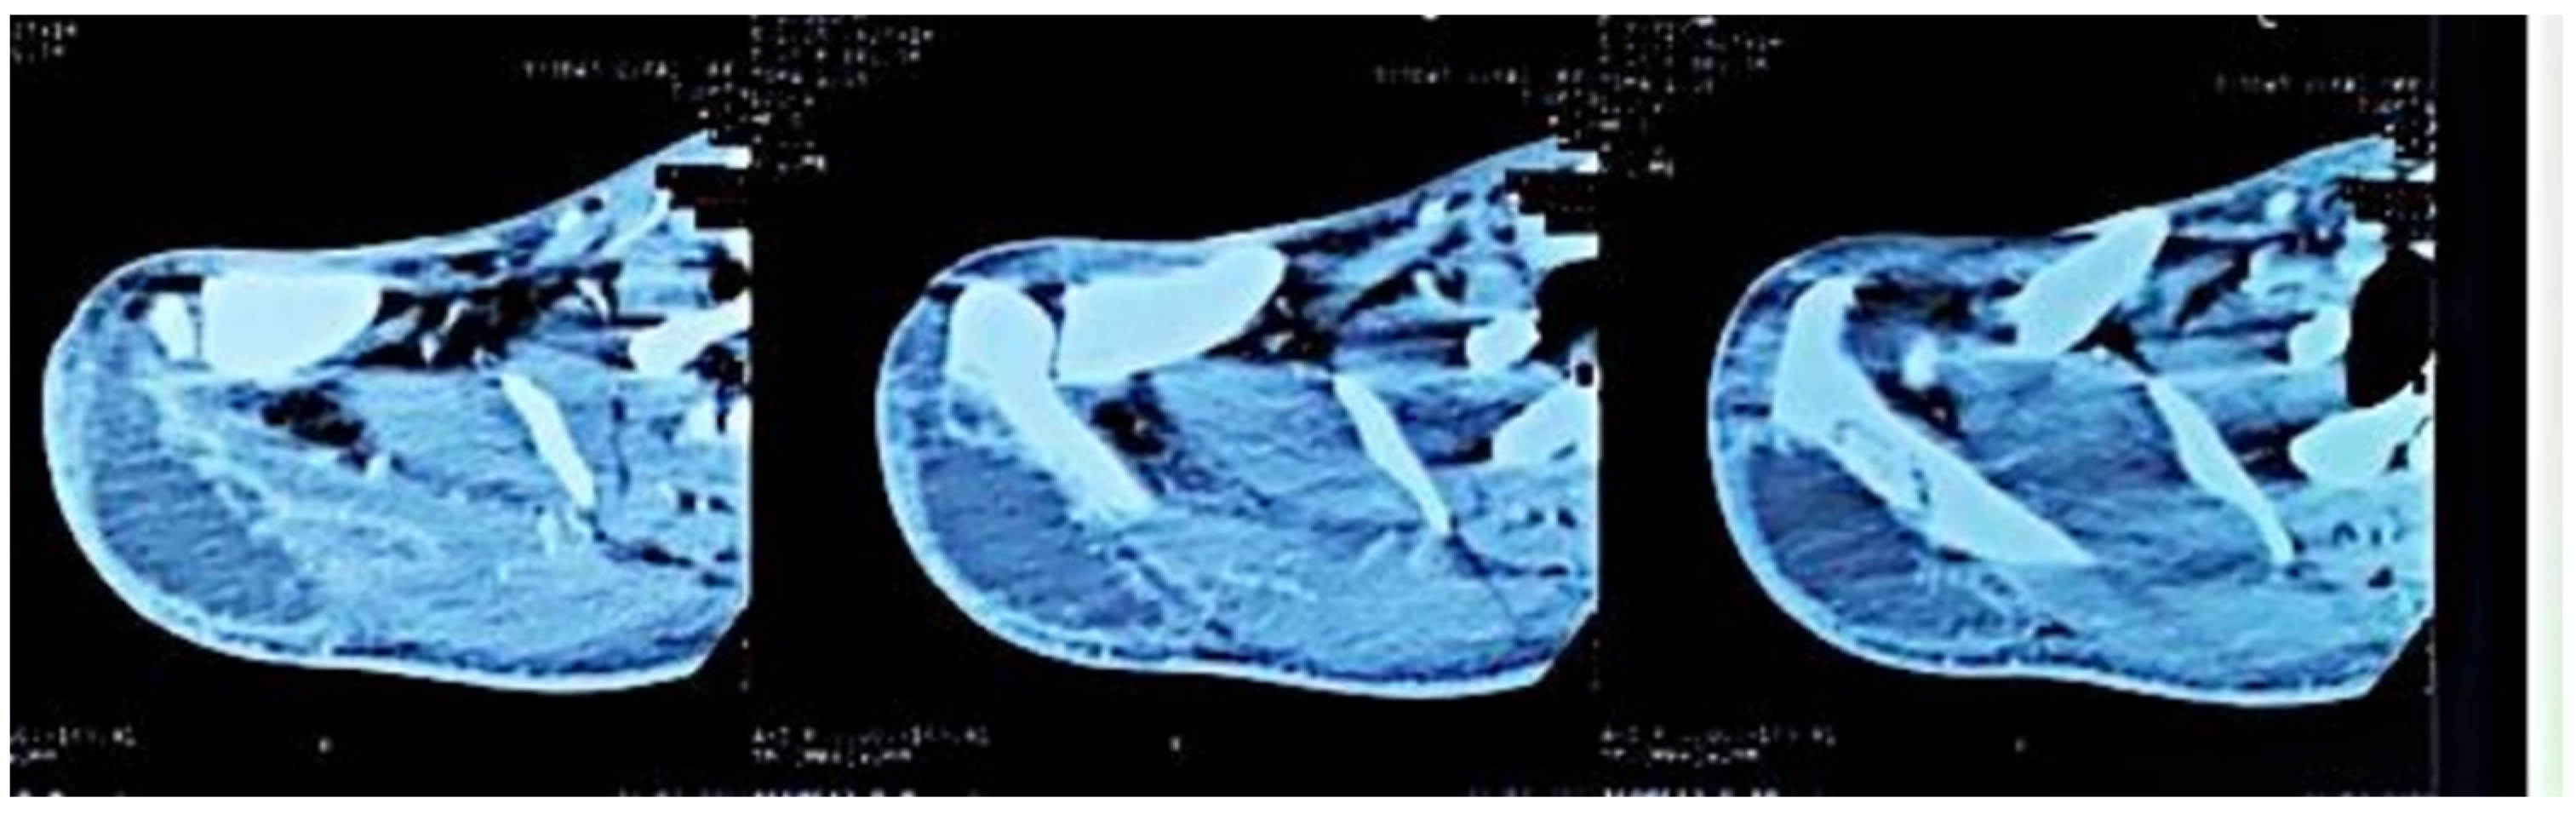

Figure 3. Axial CT sections of the shoulder, showing the lytic lesion of the distal ½ of the right scapular spine.

Figure 4. Axial sections of the shoulder CT scan, showing the deltoid collection.

Computed tomography of the right shoulder showed a lytic lesion of the right scapula with cortical rupture associated with scapular osteomyelitis (Figure 3, Figure 4 and Figure 5). The lesion was complicated by a deltoid abscess measuring 75 × 29 mm and extending over 105 mm (Figure 4), without joint effusion.

Clinically, osteoarticular TB can mimic other inflammatory and neoplastic bone lesions such as pyogenic osteomyelitis, fungal infection, multiple myeloma and metastatic disease [8]. For our case, the presence of any other germ was ruled out by pus culture and even multiplex PCR. The radiological features of skeletal TB are not specific. They may vary from lytic lesions and periarticular osteoporosis to bone marrow oedema, joint effusion, tenosynovitis and soft tissue collections [9], as in our patient, in whom a CT scan of the shoulder revealed bone lysis of the ½ distal scapular spine with cortical rupture and deltoid collection.